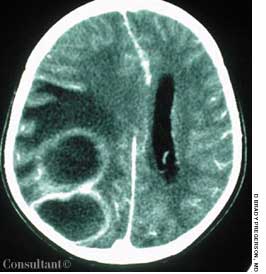

A 54-year-old woman with a history of hypertension presented with a worsening headache and a left hemisensory defect. A CT scan of her head without contrast showed a right parietal hemorrhage with spreading edema; the masslike effect caused shifting of the midline to the contralateral side. The patient gradually became comatose and required intubation for airway protection. Intravenous corticosteroids were administered to decrease the effect of the lobar hemorrhage. Fever developed 3 days after admission.